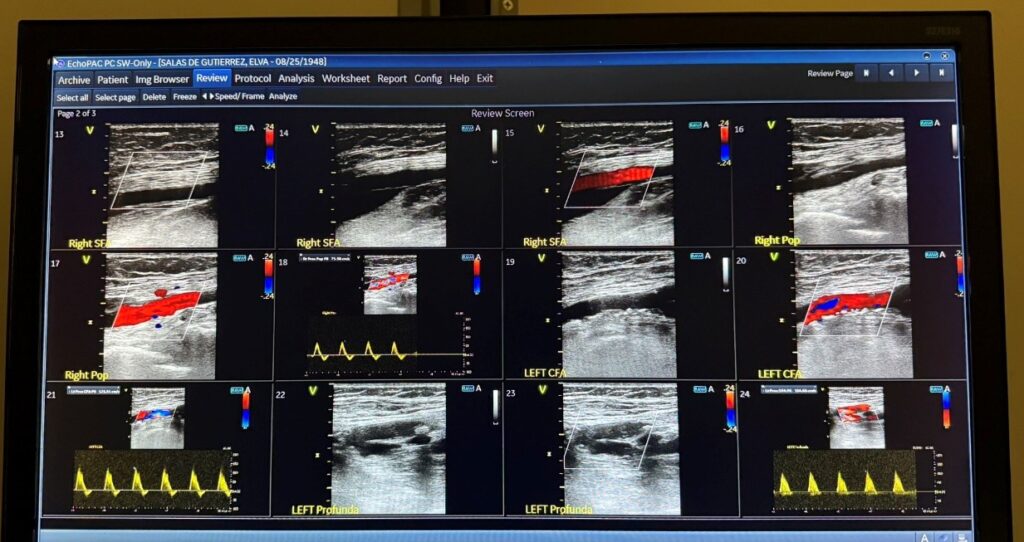

Arterial and Venous Doppler Ultrasound

Arterial and Venous Doppler studies are non-invasive ultrasound tests that use sound waves to evaluate blood flow in the arteries and veins of the lower extremities (legs)…